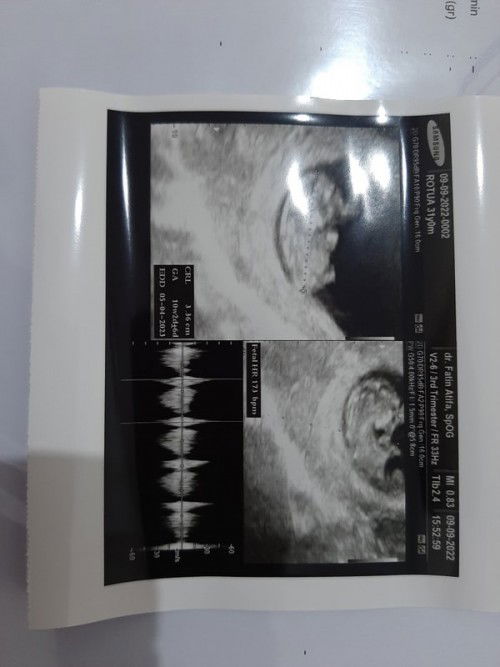

Ganti dokter & Tenpat USG